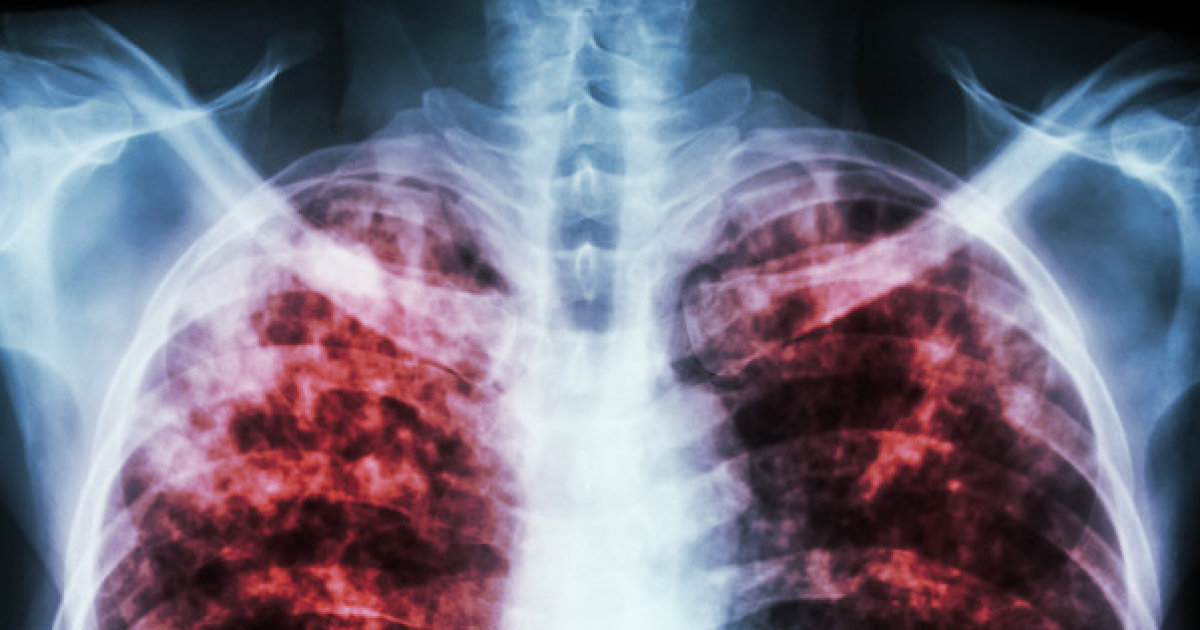

Tuberculosis

Among the more common causes of pleural effusion is tuberculosis, which is an infectious disease that mainly affects the lungs but can spread to other areas of the body like the kidneys, spine, or brain. Even if patients infected by this disease, it's possible they won't get sick. The only way they'll suffer from pleural effusion is if the infection has caused them to become sick. While this problem was once a leading cause of death in the country, it has become easy to treat over the past half-century. This infection is caused by a type of bacteria known as Mycobacterium tuberculosis. This bacteria travels through the air before it enters into the lungs. While this is considered an infectious disease, the only way for it to spread is if someone spends a substantial period in contact with the contagious individual. The main symptoms associated with tuberculosis include a severe cough that lasts for more than two weeks, coughing up blood, pain in the chest, fever, chills, weight loss, and a loss of appetite.